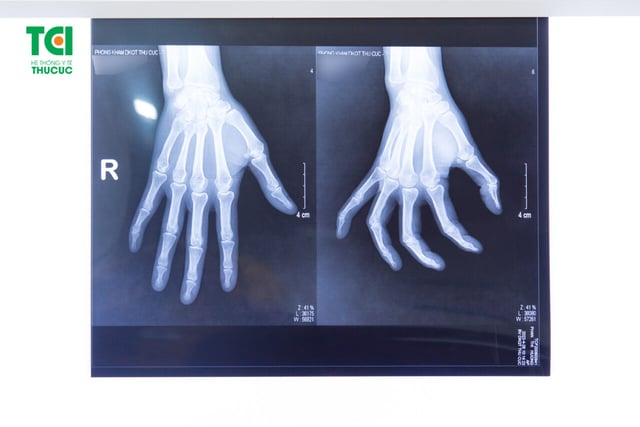

Đau đầu ngón tay: nguyên nhân, chẩn đoán và cách điều trị

Đau đầu ngón tay có thể là do chấn thương ở ngón tay và bàn tay (vết cắt, trầy xước, gãy xương hoặc nhiễm trùng) hoặc một số bệnh trạng nhất định.  Đầu ngón tay rất nhạy cảm với các kích thích vì chúng có nhiều nhiều thụ cảm và các thụ thể nhiệt độ […]